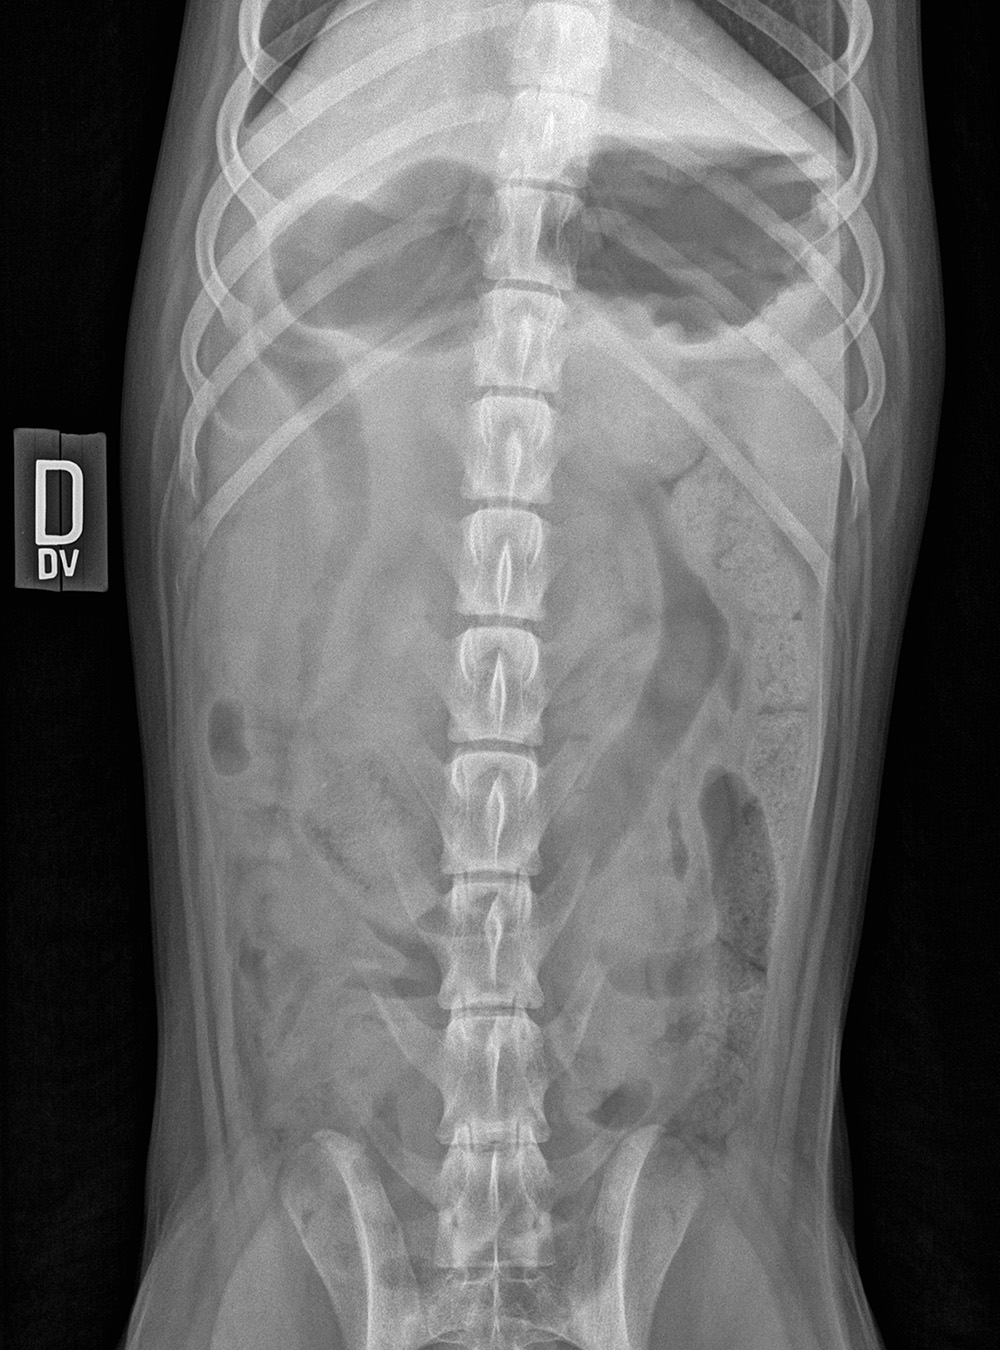

Ici, au Québec, noël rime avec dinde. La propriétaire de cette jeune labrador croyait bien faire en lui offrant le restant de sa farce. Une blague de mauvais goût selon la chienne, qui ne cesse depuis de refaire la couleur du plancher de la cuisine. Mais ce que l’histoire ne dit pas, c’est que la poubelle – qui n’avait pas été changée depuis belle lurette – aurait aussi été vidée, dans la nuit de noël, alors que tous les yeux étaient rivés vers le ciel. Est-ce un autre coup de Rudolph ? Malgré une certaine hésitation, vous n’avez pas pris de chance. Vous avez suggéré des radiographies. Quelle bonne idée !